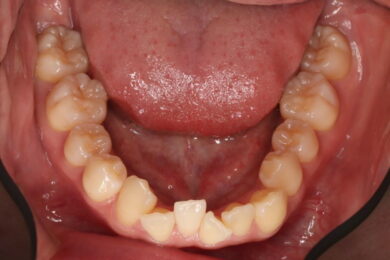

八重歯・叢生 マウスピース矯正(インビザライン)26歳女性 非抜歯

「前歯のガタガタ(叢生)と八重歯を治したい」を主訴に来院された患者様です。上下の歯にIPRを加え、歯列弓の拡大を行い、非抜歯で前歯のガタガタを整えました。顎間ゴムを用い、咬み合わせも改善されています。アライナーの装着時間が長く、チューイをしっかり使用していただけたため、非常に短時間で仕上がりました。

• 治療前